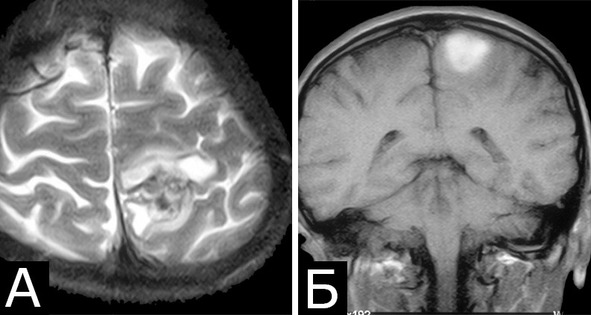

Течение заболевания и обследование: Начало заболевания за 2 месяца до госпитализации в виде тонических судорог в правой ноге. В течение последующих двух месяцев – около 20 аналогичных приступов. При МРТ выявлена КМ в области центральных извилин слева с признаками кровоизлияния (А, Б). При ЭЭГ – диффузная эпилептиформная активность с акцентом слева. При поступлении очаговая неврологическая симптоматика отсутствует.